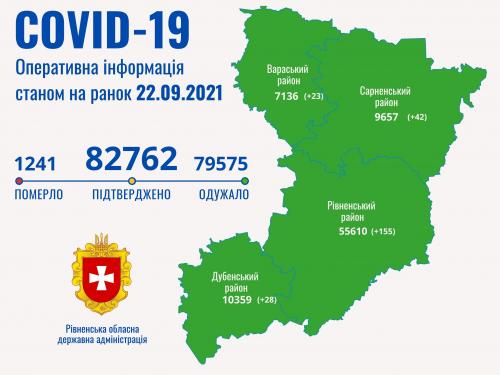

Пів тисячі - у важкому стані, 9 жителів Рівненщини померли за добу від коронавірусу